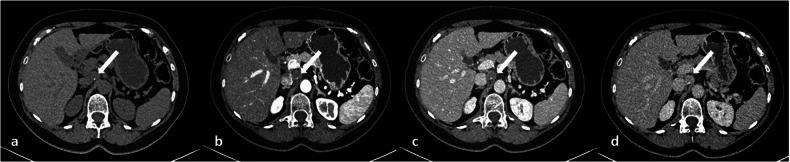

Benign nerve sheath tumors presenting as solitary retroperitoneal masses (RBNSTs) pose a complex diagnostic challenge for multidisciplinary teams regarding differential diagnosis, staging, and treatment planning. This article reviews the role played by different imaging techniques in assessing RBNSTs and elucidates their typical pathological features with a particular emphasis on the correlation between imaging and histological findings. Furthermore, some examples of retroperitoneal tumors that merit consideration in the process of differential diagnosis based on cross-sectional investigations (CSIs) are reported. The correlation between tissue architecture and appearance on imaging can help increase the accuracy of differential diagnosis with other retroperitoneal neoplasms at CSIs.

表现为孤立性腹膜后肿块的良性神经鞘瘤(RBNSTs)对多学科团队在鉴别诊断、分期和治疗规划方面构成了复杂的诊断挑战。本文回顾了不同成像技术在评估RBNSTs中所起的作用,并阐明了其典型的病理特征,特别强调了成像与组织学结果之间的相关性。此外,还报告了一些在基于横断面检查(CSI)进行鉴别诊断过程中值得考虑的腹膜后肿瘤实例。组织结构与成像表现之间的相关性有助于提高CSI时与其他腹膜后肿瘤鉴别诊断的准确性。